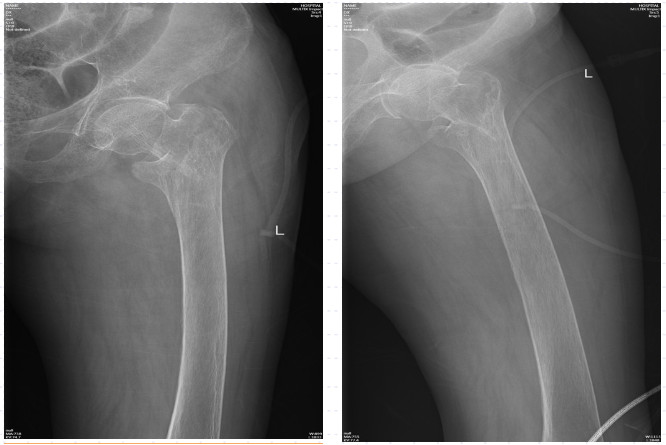

近日,88歲高齡的陳奶奶因滑倒摔傷,臀部著地,當(dāng)即感到左髖部疼痛,無法站立行走,活動明顯受限。陳奶奶的家人發(fā)現(xiàn)后立即將她送至我院急診科進(jìn)行救治。拍片后提示為左股骨粗隆間骨折,需要手術(shù)治療。

在詢問陳奶奶的家屬后得知,陳奶奶年事已高,疾病纏身,除了有冠心病、心房顫動、全心衰等心臟方面的問題,同時合并有老年性骨質(zhì)疏松、主動脈硬化、甲狀腺功能亢進(jìn)(未進(jìn)行治療)、貧血、凝血功能異常等基礎(chǔ)疾病。另外,陳奶奶曾于2020年在我院順利完成了“右側(cè)股骨粗隆間骨折閉合復(fù)位APFN內(nèi)固定術(shù)”,術(shù)后恢復(fù)良好,3年來生活基本恢復(fù)正常。

不幸的是,這次受傷造成了左股骨粗隆間骨折,陳奶奶將迎來第二次的髖關(guān)節(jié)手術(shù)!此次手術(shù)的風(fēng)險比上一次更高,術(shù)后治療與康復(fù)也更具有挑戰(zhàn)性!

術(shù)前